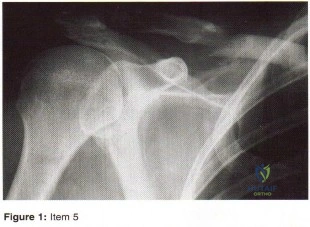

- C5 radiculopathy

- Subscapularis rupture

- Glenohumeral arthrosis

- Rotator cuff arthropathy

- Suprascapular nerve compression at the spinoglenoid notch

- Subscapularis rupture

- Type III SLAP lesion

- Disruption of capsular shift

- Isolated traumatic subluxation

- Injury to the axillary nerve after dislocation

- Displaced labral tear

- Tear of the rotator cuff

- Fracture of the glenoid rim

- Palsy of the axillary nerve

- Palsy of the musculocutaneus nerve